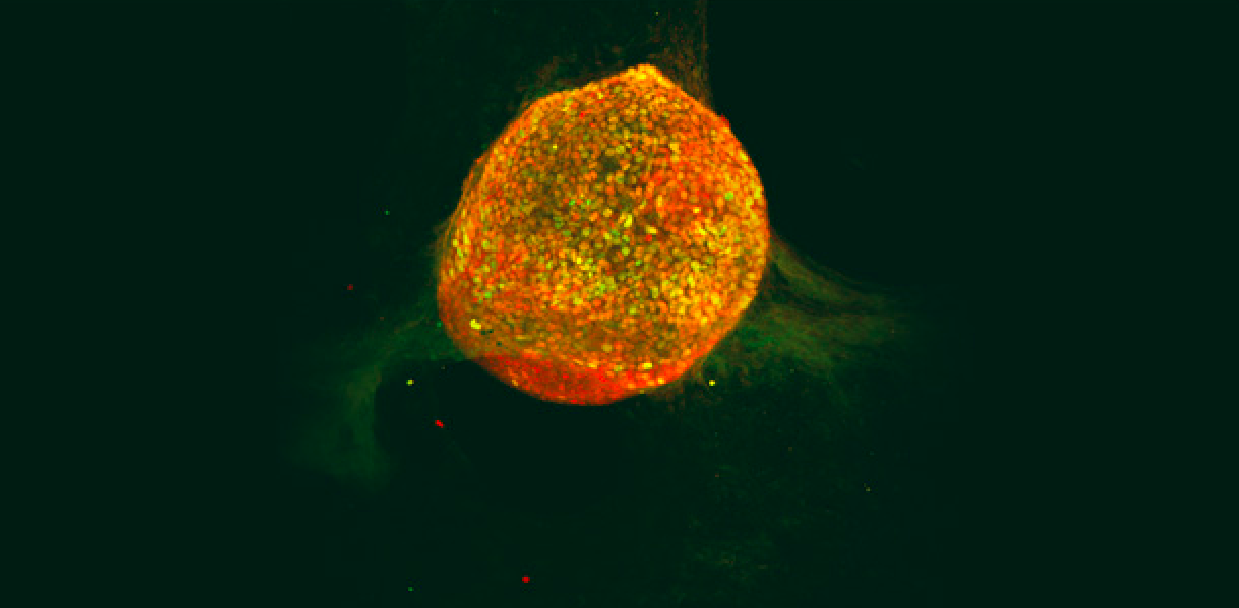

Imaging of islet-like cluster cells

Stem cell-derived pancreatic islet clusters